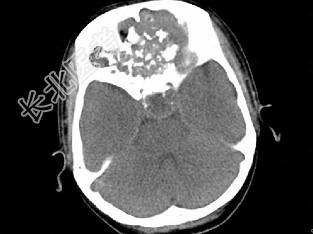

- 单项选择题男,26岁, 进行性鼻腔阻塞、流涕来院就诊,近两年持续性头痛、头晕.如图所示筛窦区占位灶应诊断为 ( )

A、脊索瘤伴左上颌窦炎

B、软骨瘤伴左上颌窦炎

C、骨化性纤维瘤伴左上颌窦炎

D、骨结核伴左上颌窦炎

E、骨纤维异常增殖症伴左上颌窦炎